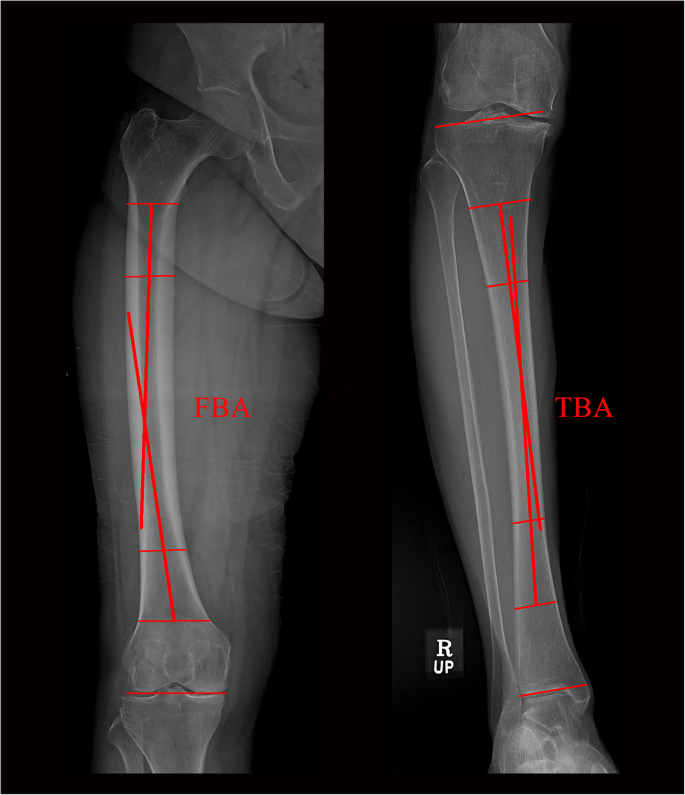

The femoral bowing angle (FBA) and tibial bowing angle (TBA) were determined from preoperative standardized full-length hip–knee–ankle weight-bearing anteroposterior (AP) radiographs, measuring 14 × 51 in.. Full-length weight-bearing radiographs were obtained with the subjects standing barefoot in a position in which the patella was oriented forward (Fig. 2). Femoral bowing was defined as an FBA > 3° or < − 3° [23]. Tibial bowing was defined as a TBA > 2° or < − 2° [19, 24]. All lateral bowing was recorded as positive, whereas medial bowing was recorded as negative.

Preoperative full-length (14 × 51 in. grid cassette) radiograph showing the measurement of the femoral bowing angle (FBA) and tibial bowing angle (TBA). The FBA was defined as the angle between the line connecting the points bisecting the femur at 0 cm and 5 cm below the lowest portion of the lesser trochanter and the line connecting the points bisecting the femur at 5 cm and 10 cm above the lowest portion of the lateral femoral condyle [23]. The TBA was defined as the angle between the line connecting the points bisecting the tibia at 5 cm and 10 cm from the highest portion of the lateral tibial plateau and the line connecting the points bisecting the tibia at 5 cm and 10 cm from the lowest portion of the tibial plafond [19].